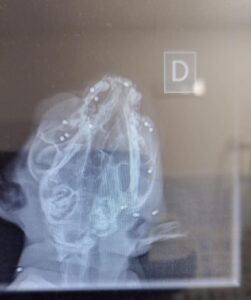

Il gatto è stato immediatamente portato presso una clinica veterinaria. La radiografia (che potete vedere in calce al presente articolo) ha evidenziato numerosi pallini metallici nel cranio dell’animale riconducibili, secondo i veterinari, a un fucile ad aria compressa. Fortunatamente l’animale è stato soccorso in tempo, ma le ferite riportate sono gravi.